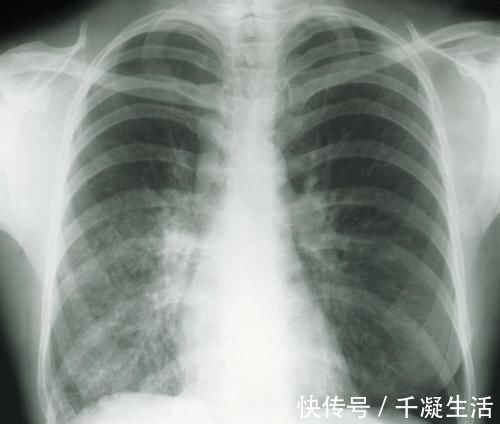

两年前,陈女士在体检中意外查出肺结节,且双肺多发,这让有肺癌家族史的陈女士慌了神。

近期,陈女士来到医院复查,薄层CT扫描结果显示,陈女士左肺为磨玻璃结节,且有增大现象,考虑恶性可能度高。

术后病理结果显示,陈女士体内的肺结节,最大的仅有0.9cm,但已发展为早期浸润肺癌,一个为原位腺癌,0.4cm,其他的均为炎症性结节。

肺磨玻璃结节一般是在做胸部CT时发现,表现为密度轻度增高的云雾状淡薄影或圆形结节,样子像磨砂玻璃,所以叫磨玻璃影。可以是弥漫性散在生长,也可以聚集在局部,看起来就像一个小磨玻璃结节。